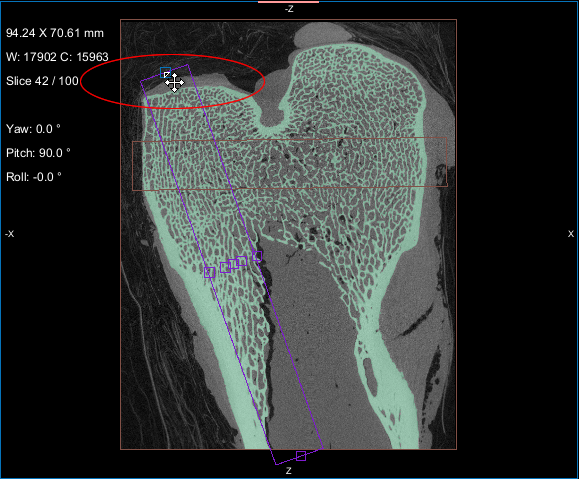

This Bone Analysis tutorial provides step-by-step instructions for segmenting a proximal femur and for computing vector-based fields of anisotropy and scalar-based maps of volume fraction. Additional topics in this tutorial describe how to compute high-resolution maps from data sub-volumes and how to evaluate the computed maps.

Screen capture of the completed tutorial